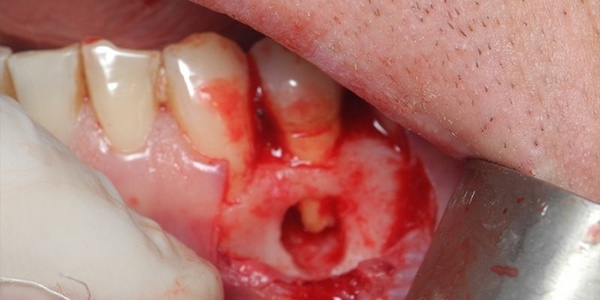

Фото 2. Гнойное воспаление дёсенного кармана на тяжелой стадии. На десне образуется язва.

- Выпадение зубов из-за их системного расшатывания

При тяжёлой форме заболевания, когда глубина пародонтального канала превышает 6 мм, а дёсны гноятся и кровоточат, происходит поражение периодонтальной связки. Чем оно глубже и обширнее, тем сильнее расшатывается зуб. Чаще зуб подлежит удалению, но в ряде случаев возможна фиксация зуба при помощи шинирования.